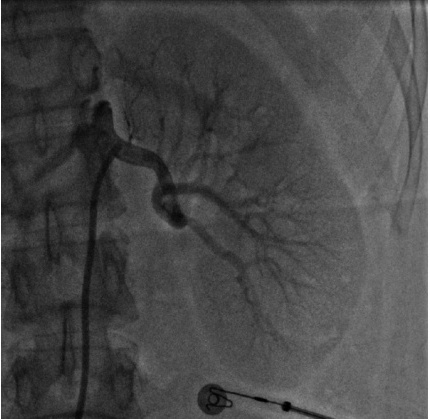

年轻女性,重度高血压伴低血钾

病史摘要:患者为 21 岁女性,1 天前因头晕测血压发现重度升高,无其他不适。1 个月前有上呼吸道感染症状,后出现颌下淋巴结肿大。既往体健,无慢性疾病、传染病、手术外伤等病史,月经规律。家族中外祖母有高血压,否认一级亲属高血压及其他遗传性疾病史。 诊疗过程:入院查体无明显异常体征。辅助检查提示血钾低,醛固酮、肾素活性增高,尿蛋白微量。肾脏、肾上腺等超声部分未见明显异常,眼底为 I

右肾动脉狭窄

肾血管性高血压